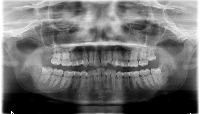

Dental Treatment Planning: The Dentistry computer vision model can be used by dentists and orthodontists for analyzing dental X-rays to identify teeth numbers and conditions like implant, root canal, or crown. By having automatic classification, it will improve the efficiency and accuracy of the treatment planning process.

Dental Education and Training: The model can be utilized as a learning tool for dental students, helping them to familiarize themselves with tooth numbering, implants, crowns, and root canals. This could be implemented in virtual classrooms or integrated into educational mobile applications.

Dental Insurance Claim Processing: The Dentistry computer vision model can be employed by insurance companies to automatically process dental claims. The model can identify the specific treatments or procedures (such as root canals or implants) from the dental X-ray images, leading to faster and more accurate claim processing.

Dental Record Management: Clinics and hospitals can use the Dentistry model to streamline their dental patients' record management by automatically categorizing X-ray images based on tooth number and treatment type. This will help in better organization of patient records and ease of access for future reference.

Dental Research and Analytics: The model can be valuable for dental researchers in the field of oral health analytics. By analyzing large datasets of dental X-ray images, the model can help identify patterns and trends for different treatments and tooth conditions, providing valuable insights for better oral care and health.